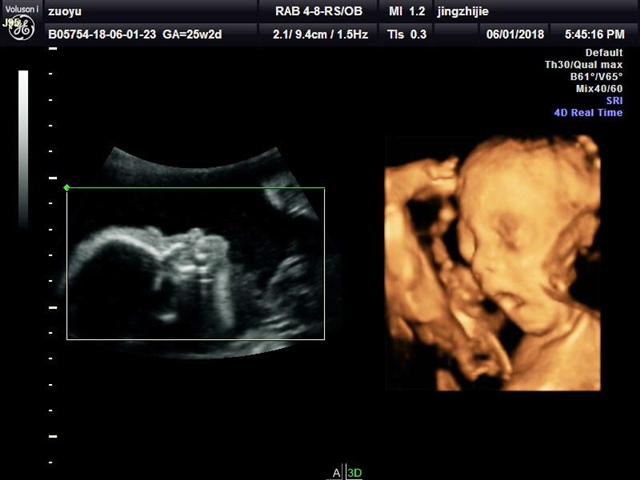

孕22周+3天

张嘴打哈欠那张萌到我了😄

叮噹猫[帖主]:哈哈……我们这边医院每次B超我们什么都看不到,我特意去的外面摄影工作室拍的四维,6个多月以来第一次见到宝宝的影像,打哈欠刚好拍成视频了,第一个六一节还纪念了一下